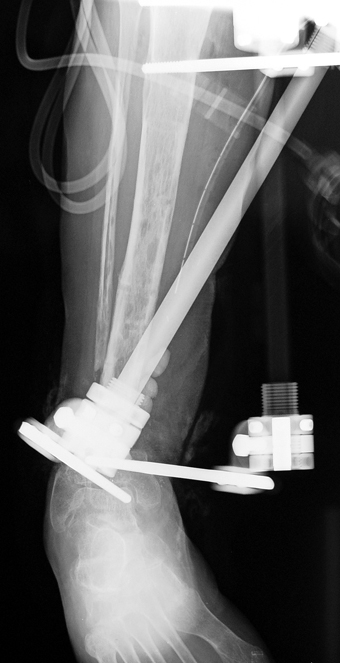

Recently, ilizarov techniques which is basis depend on distraction osteogenesis , bone segment transport or acute shortening after the resection at the site of pseudarthrosis combined with lengthening at another level of bone have been used. These treatment techniques may include some advantage for problems of infection, leg-length discrepancy, soft-tissue loss, and joint contracture.

Case 1